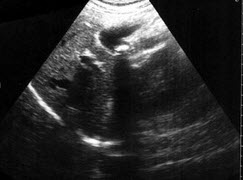

某患者自诉乳腺可触及一包块,光滑可移动,超声图像如图,诊断为()

A.纤维瘤

B.囊肿

C.乳腺癌

D.小叶增生

E.乳腺导管扩张